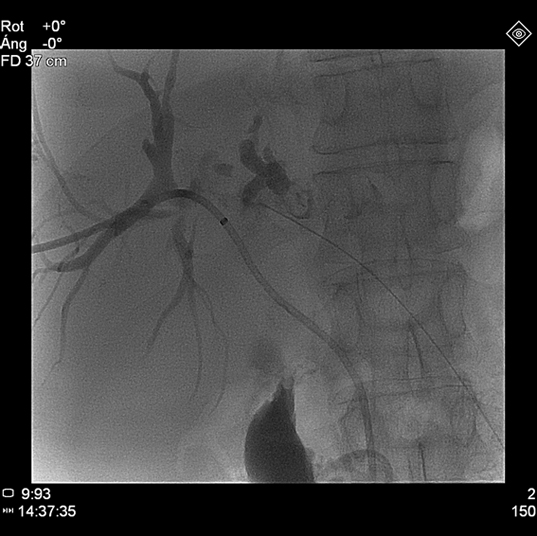

Percutaneous transhepatic cholangiography was then performed after ciprofloxacin prophylaxis. Internal-external drainage was placed during the intervention. During the procedure, solid material occupying the bile duct was unexpectedly identified [Table/Fig-1]. Pathological analysis demonstrated the presence of solid tumour fragments of adenocarcinoma [Table/Fig-2]. At this time, microbiological study of biliary fluid did not detect bacterial cholangitis. Given these findings, abdominal CT images were reviewed which revealed increased iodinated contrast uptake within the dilated bile duct, suggestive of bile duct tumour invasion [Table/Fig-3].

Cholangiography. Dilated biliary tract. Distal duct was not opacified due to solid material occupying the bile duct.